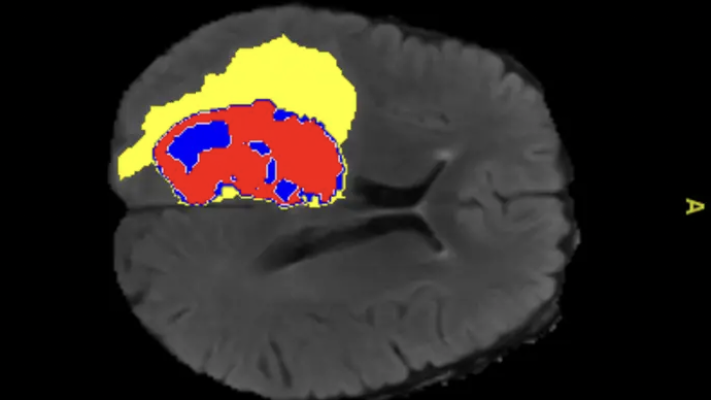

AI-annotated medical image showing enhanced tumor, tumor core and edema regions. Image courtesy of Monash University

“Traditionally radiologists and other medical experts annotate, or label, medical scans by hand highlighting specific areas of interest, such as tumors or other lesions. These labels provide guidance or supervision for training AI models.